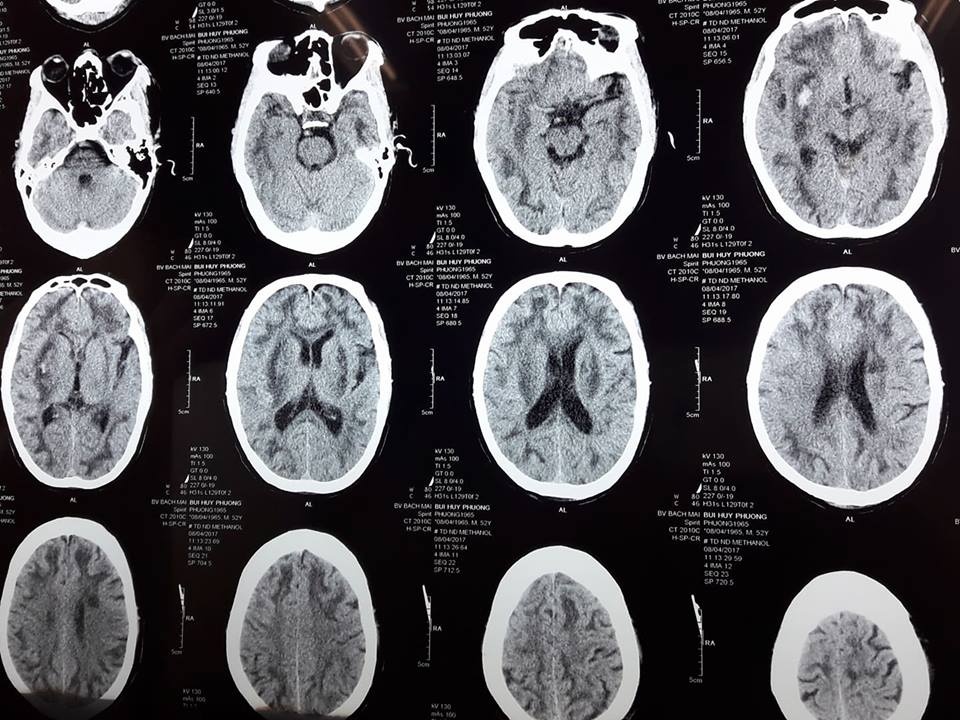

Bệnh nhân đầu tiên là nam giới, 52 tuổi ở Ngọc Khánh (Ba Đình, Hà Nội), uống rượu trước khi vào Trung tâm chống độc khoảng 24 giờ tại khu vực đường Kim Mã, La Thành. Bệnh nhân được chuyển đến Trung tâm chống độc trong tình trạng hôn mê sâu, tổn thương cả 2 bên bán cầu não, toan chuyển hoá nặng.

Xét nghiệm thấy nồng độ Methanol trong máu lên đến 45,9 mg/dl, bệnh nhân đã được trung tâm chống độc điều trị bằng tất cả các liệu pháp tích cực với một tình trạng ngộ độc methanol nặng.

Đến chiều 8/4, xét nghiệm methanol trong máu đã âm tính nhưng bệnh nhân vẫn trong tình trạng hôn mê sâu, tổn thương não nặng nề, nguy cơ di chứng và tử vong rất cao.

| Hình ảnh chụp não bị tổn thương của người đàn ông 52 tuổi bị ngộ độc rượu có methanol. Ảnh: Bác sĩ cung cấp. |